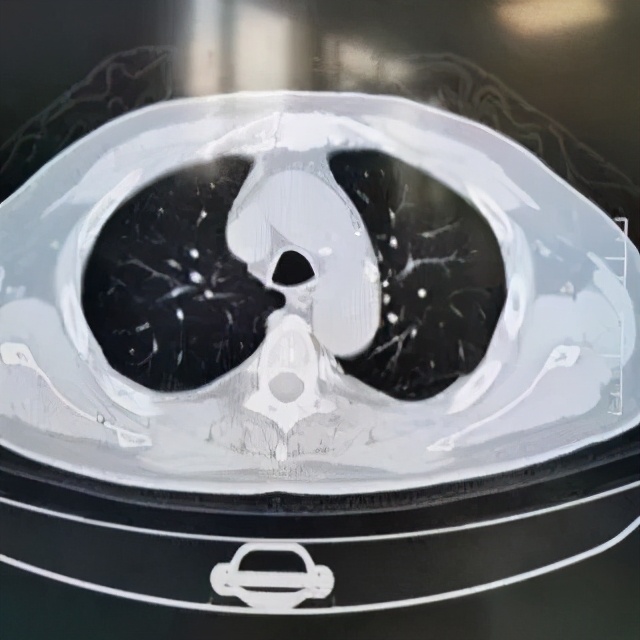

本院胸部CT(2019-08-30)示: 双肺弥漫性间质性改变,有网格状改变、毛玻璃影、局部有支气管牵拉形成支气管扩张的表现。

追溯患者2018年体检胸部CT(2018-1-22) :两肺下叶轻度间质增生,无显著双肺弥漫性间质改变。而且近一个月出现气促症状、低氧血症,说明间质性病变有活动性。